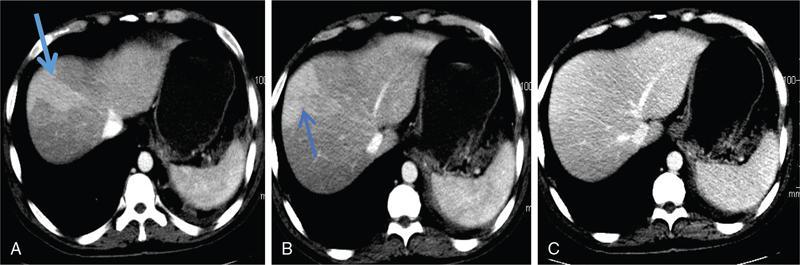

CT

Assessment of hepatic steatosis using CT is based on the measurement of attenuation value of liver parenchyma, expressed as Hounsfield units (HU)

Attenuation difference between liver and spleen on unenhanced CT scan has been the most commonly used

Cut-off value of attenuation difference to detect moderate to severe degree hepatic steatosis-9